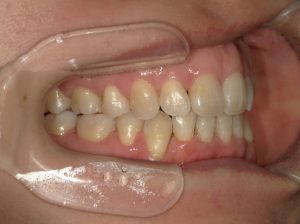

治療前→治療後(左側方)